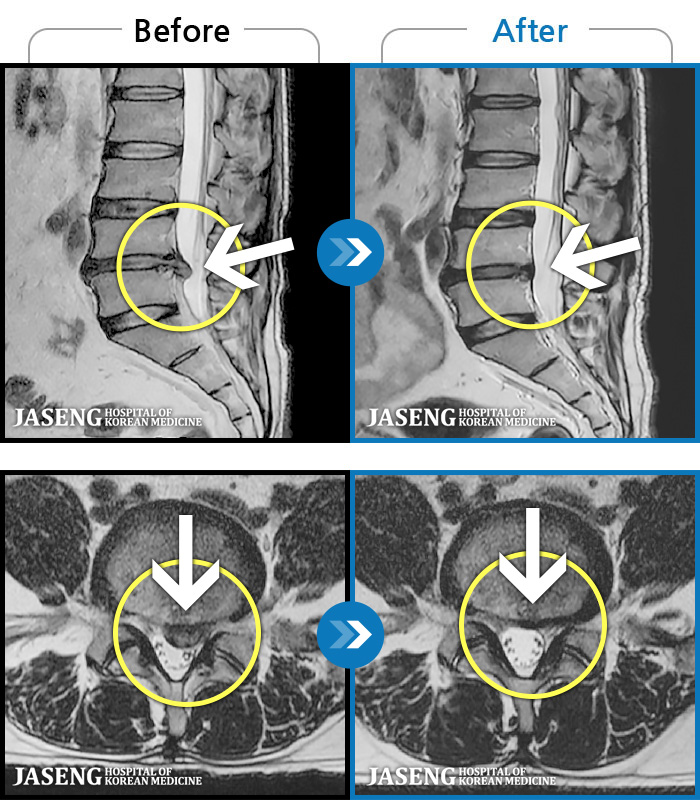

Before

After

환자에게 사전 동의를 받아 동일 조건에서 촬영되었습니다.

개인에 따라 치료 후 부작용이 발생할 수 있으니 의료진과 상담 후 치료를 진행하시기 바랍니다.

처음 내원 시 허리와 좌측 골반 통증이 심한 상태였습니다.

양측 엉덩이 저림 통증과 활동 시 허리 통증이 증가했습니다.